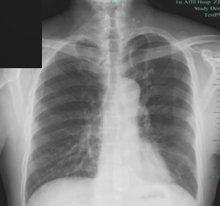

The authors started with a standard 3-port VATS approach dissecting the hilum first to skeletonize the left superior pulmonary vein. V3a was identified, dissected, and divided after suture ligation at the proximal end and harmonic distally. Station 11, 12 lymph nodes were dissected. A3 was identified and divided with staplers. Anterior segment bronchus deeper to the artery was dissected and divided using staplers. V4+5 draining to lingula was safeguarded. S3 segment was demarcated, preserving adjacent segmental veins. Anterior segmentectomy was completed using staplers. Postoperative period was uneventful. The lung was completely expanded on an X-ray chest. The intercostal drain was removed on the third day and the patient was discharged.